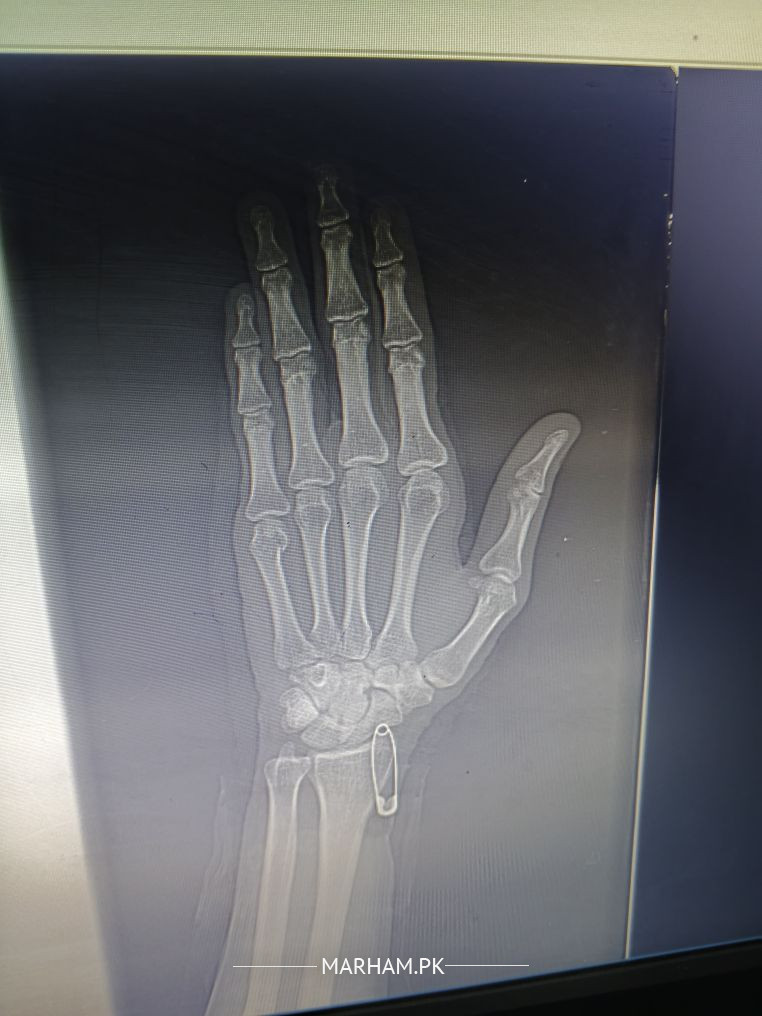

hath me dard hai aap dekh kr bhataen koi bone facture to nhi hai

fracture 5th metacarpal head..need lateral and oblique views as well and need reduction and slab

Agreed with my other colleague, looks fracture of little finger base, need to correlate with physical examination findings. See any orthopedic Surgeon near you for proper assessment and than management.